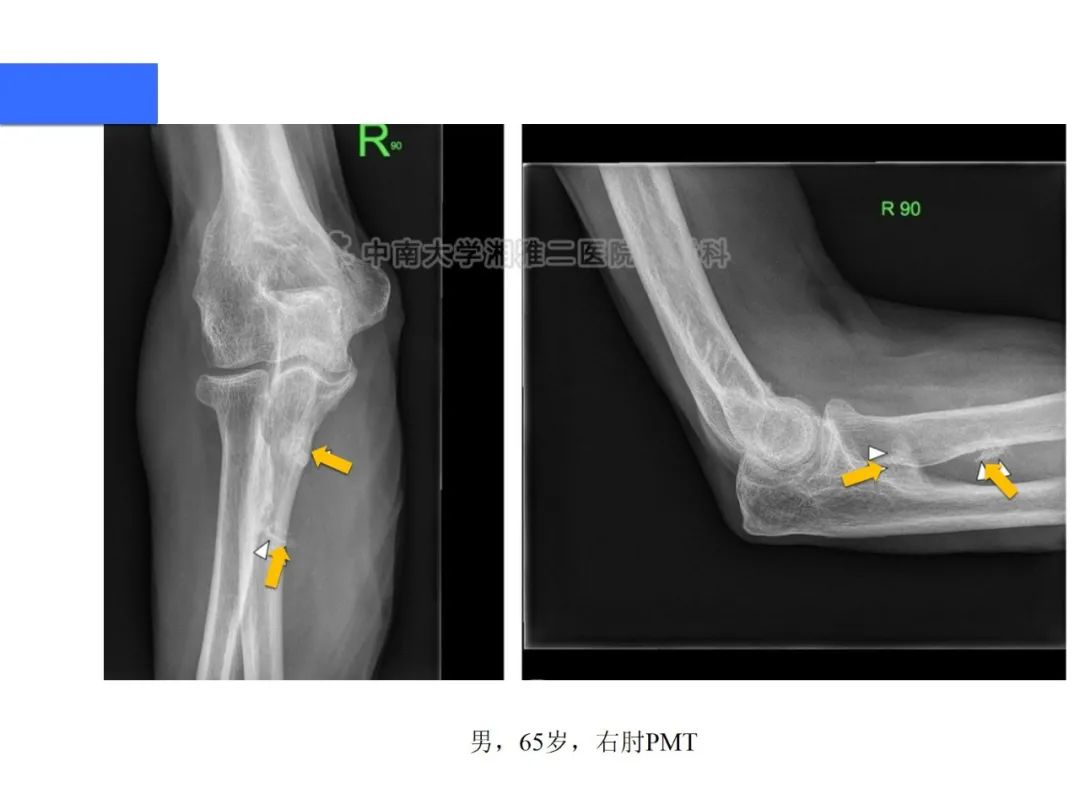

【病例】磷酸盐尿性间叶性肿瘤1例影像学诊断思路-3